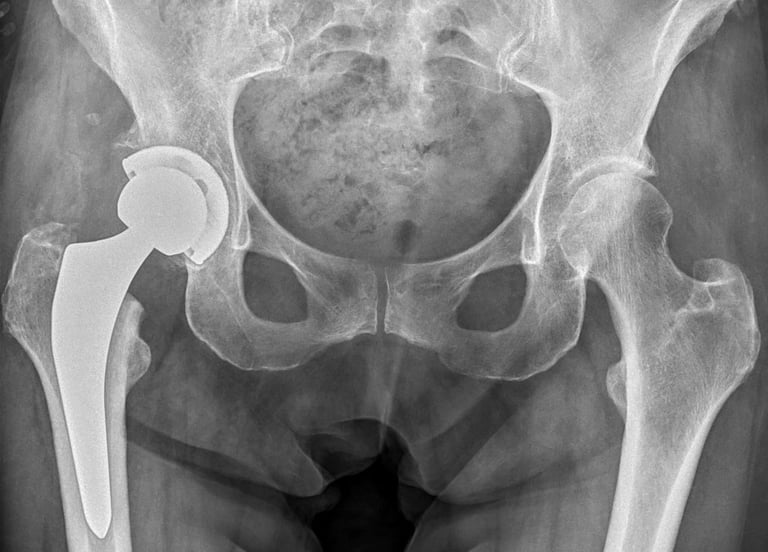

Chirurgia protesica d'anca

Impianti primari con tecnica mininvasiva ("HEROS approach")